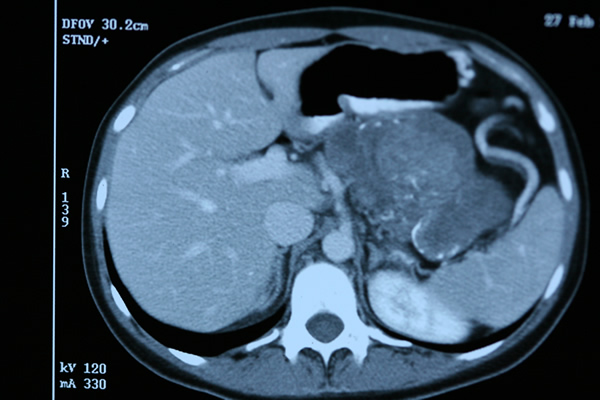

Kalıtsal olmayan risk grubundaki hastalar kronik pankreatit ve pankreas kisti olan hastalardır. Bu hastalar genellikle bilgisayarlı tomografi veya manyetik rezonans(MR) ile görüntülenerek incelenirler. Bunlara ek olarak son yıllarda gerektiğinde endoskopik ultrasonografi de uygulanmaktadır. Kalıtımsal risk grubundaki hastalara da benzer yöntemler uygulanmaktadır.

Bu tarama programlarında amaç erken kanserleri saptamak olduğu kadar kanser öncesi gelişen ve kansere dönüşebilen doku değişikliklerini saptayabilmektir. Genel olarak topluma göre 5-10 kat risk taşıyan hastalarda 50 yaşta bu tarama programlarını başlatmak önerilmektedir.

Risk taşıyan hastalarda tarama programlarında solid lezyon, kist veya PanIN-3 olarak adlandırılan problemler saptandığında cerrahi tedavi koruyucu olarak önerilmektedir.